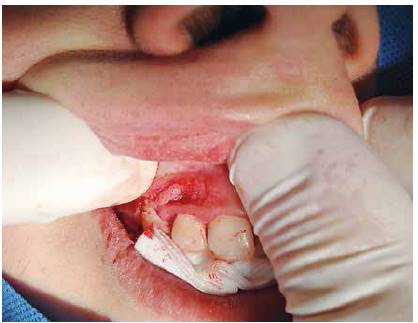

Al realizar el examen intraoral se observa un aumento de volumen de forma ovalada que va desde el margen gingival, abarcando encía adherida hasta muy cerca del fondo de vestíbulo. Esta lesión se extiende desde distal del diente 1.1 hasta mesial del 1.4. A la palpación, su consistencia es muy firme y tiene un color rosa pálido y presenta una base pediculada (Figura 1 y 2).

Se realizó una biopsia excisional de la lesión bajo anestesia local con vasoconstrictor. Al momento de retirar la lesión y realizar la biopsia, se observó una zona de exostosis ósea bajo la lesión, que se retiró en el momento de la cirugía (Figura 5).